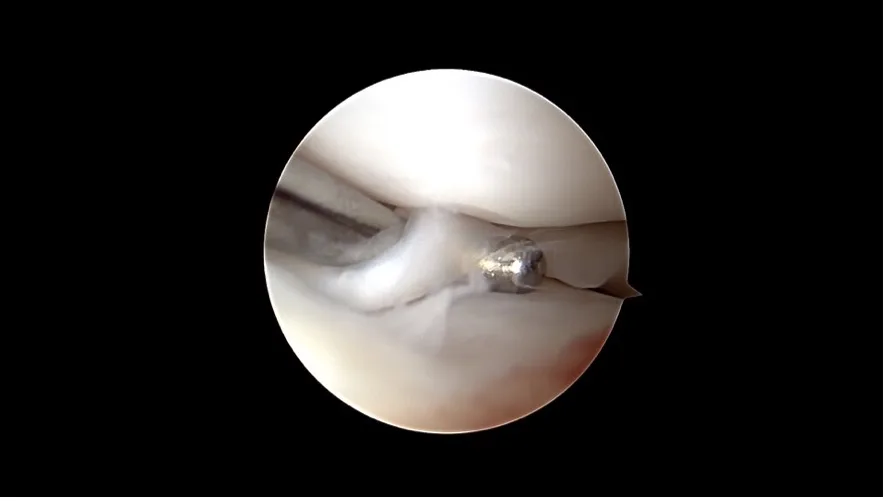

Une déchirure du ligament croisé naissante se cache sous le reste du ligament croisé, qui semble à première vue normal.

Une rupture complète du ligament croisé

Nanoscopie

Encore plus fine que l’arthroscopie, la nanoscopie utilise des instruments très petits et une imagerie haute résolution dans l’articulation. Elle est particulièrement adaptée aux petits chiens. Les deux méthodes sont mini invasives, limitent le traumatisme tissulaire et favorisent une récupération plus rapide.